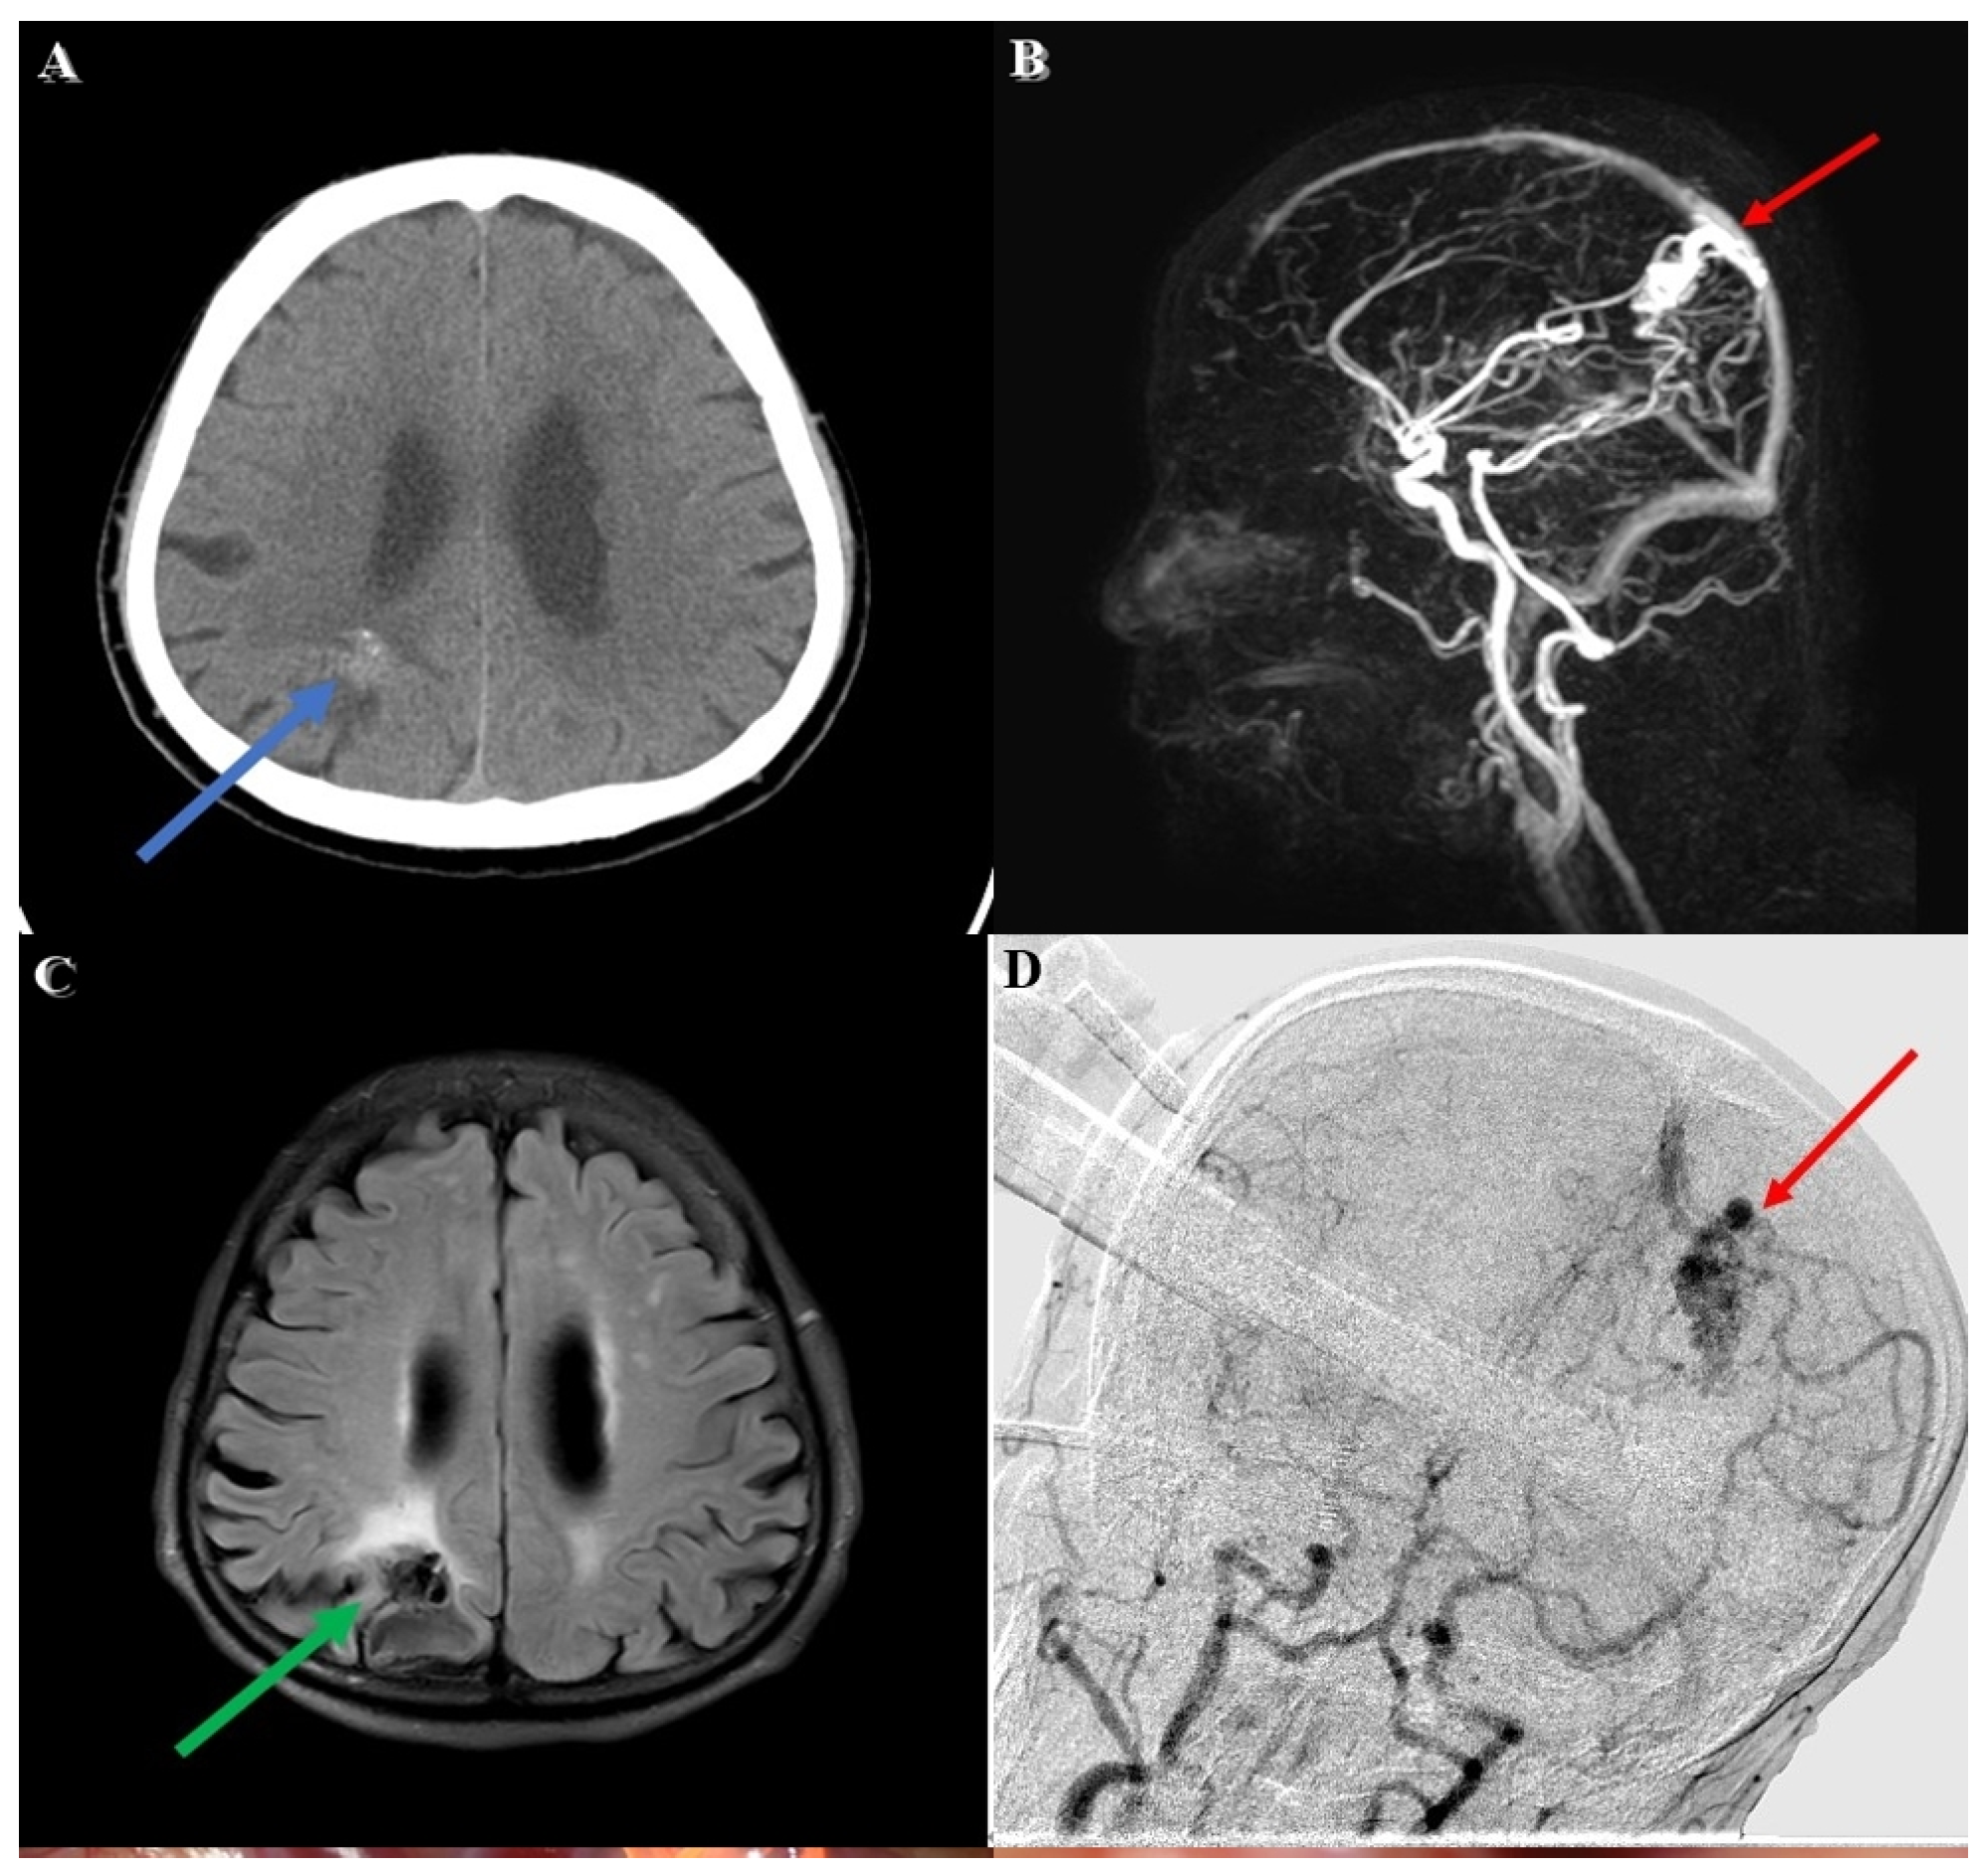

The first stage of the operation for the patient’s AVM resection was confirmative digital subtraction angiography (DSA) (Figure 1D) followed by right parieto-occipital craniotomy. After performing a dura opening, surgery proceeded to the microsurgical stage performed under a microscope (Figure 2A). With assistance from the AR technique, the feeding arteries from the posterior cerebral artery and the parietal branch of the middle cerebral artery were labeled with red and yellow color, respectively, and then projected onto the cortex. Furthermore, the AVM nidus was coded with blue color for identification (Figure 2B). In the next dissection and resection stage, we adjusted the focal length and hologram setting to clarify the surgical field. After confirmation of the spatial relationship in the angiographic complex, both coagulation and clipping were performed to obliterate the feeding artery (Figure 2C). After the clipping and coagulation of the first feeding artery from the middle cerebral artery, we proceeded to obliterate another feeding artery from the posterior cerebral artery (Figure 2D). Eventually, the AVM nidus got resected after both the feeding arteries were obliterated.

Figure 2. Microsurgery under assistance of AR technique. (A) Surgical field without AR hologram projection. (B) AVM nidus and feeding arteries were labeled with different color (blue: AVM nidus; red: feeding artery from middle cerebral artery; yellow: feeding artery from posterior cerebral artery); the red arrow also indicates feeding artery from middle cerebral artery. (C) Clipping and coagulation of the feeding artery. (D) Obliteration for another feeding artery from posterior cerebral artery; the green arrow indicates clip for feeding artery elimination.